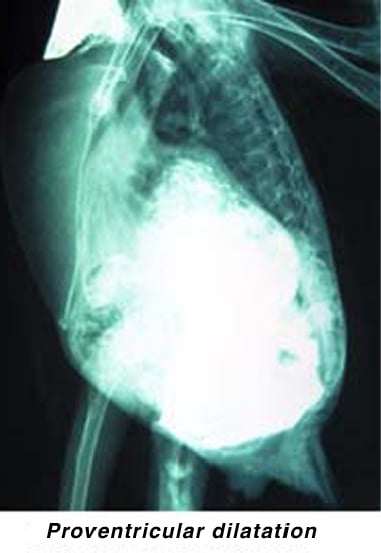

Clinical signs may suggest a case of PDD. To rule out other problems, it is best to start with a complete physical examination by an avian veterinarian. Blood tests (a complete blood cell count and blood chemistry profile) and whole-body radiographs (X-rays) should be performed. A barium contrast study can be useful in suspicious cases, as it may demonstrate a dilation of the proventriculus.